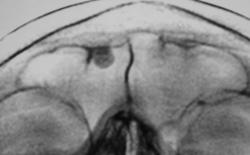

Иллюстрации 3, 4, 5, 6. Варианты скиалогической картины лобной пазухи «с увеличением изображения»

При анализе иллюстраций 3, 4, 5, 6 чётко дифференцируется неоднородность тени остеомы за счет очаговых уплотнений.